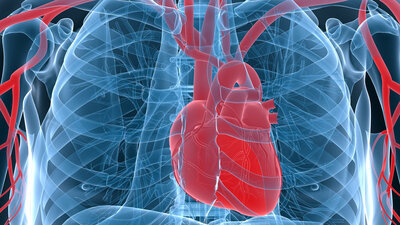

Kardiale autonome diabetische Neuropathie

Diabetes kann auf längere Sicht zu Nervenschäden am Herz führen, mit teils gfährlichen Folgen. zum Artikel